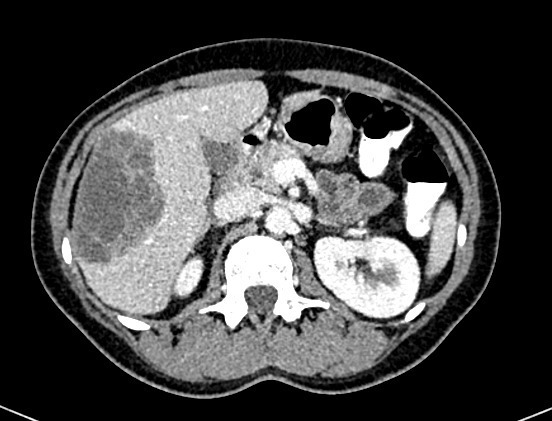

Vous avez fait réaliser l’examen suivant, confirmant le syndrome occlusif (figures 1 et 2) : Fig. 1 (source : M. Roulleaux Dugage)Fig. 2 (source : M. Roulleaux Dugage)

Question 4 - Concernant cet examen d’imagerie, vous pouvez dire :

Il s’agit bien d’un scanner abdomino-pelvien injecté, au temps portal, mettant en évidence une volumineuse masse du côlon droit associée à au moins une masse hépatique d’allure secondaire. Pour rappel : – au temps artériel : opacification de l’aorte, de la périphérie du rein ; – au temps portal : prise de contraste massive du parenchyme hépatique et rénal ; – au temps veineux : prise de contraste veine cave inférieure…